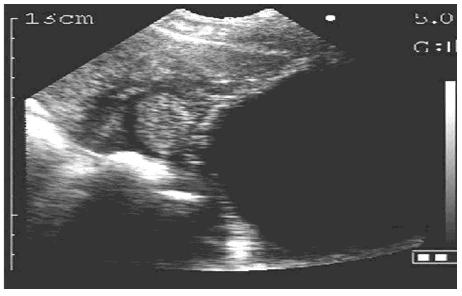

4. 结果判定

- 怀孕图像

- 未孕图像

- 膀胱图像

较大的黑洞为膀胱,探头放的太靠后